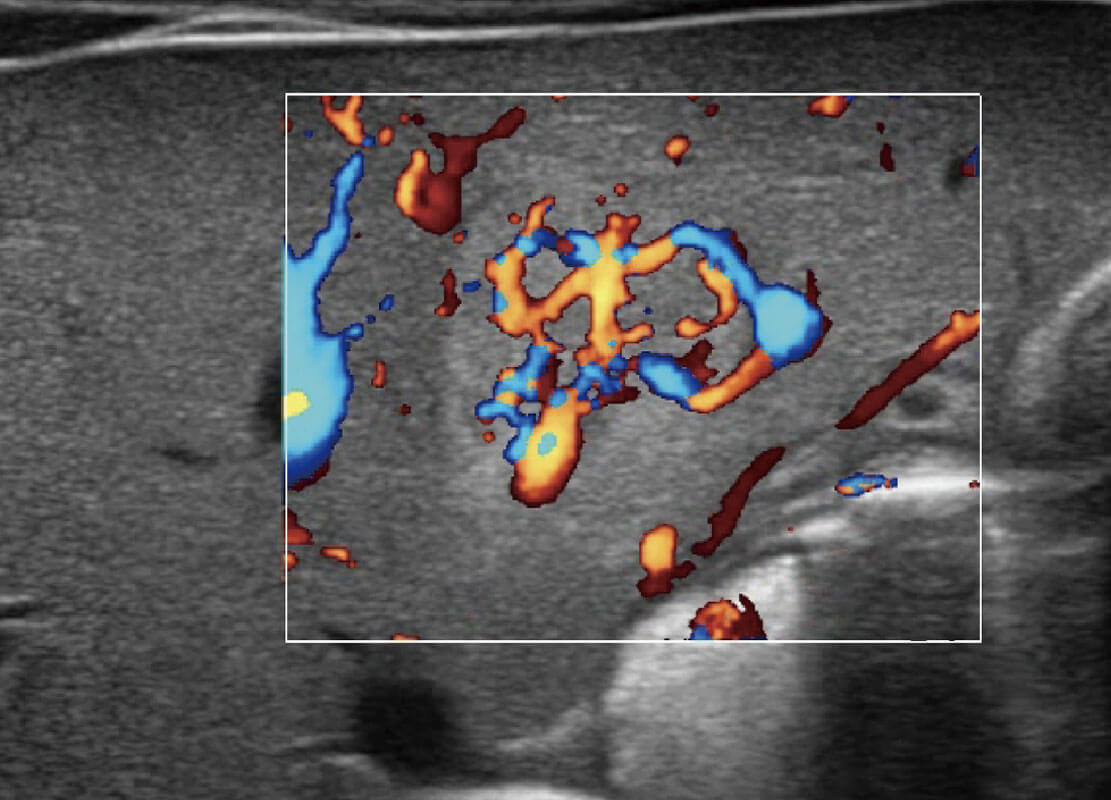

P60搭载一系列胎儿心脏成像技术,实现精细的胎儿心脏评估。

四腔心血流

胎心容积成像